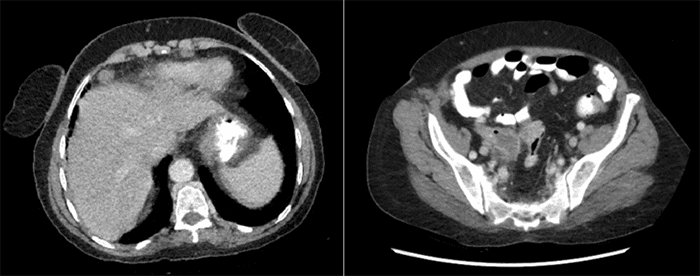

The patient missed several appointments and presented to the emergency room two months later with progressive right-sided pain, loss of appetite, and an unintentional weight loss of 8 kg. A repeat CT scan demonstrated the persistent appendiceal mass and a new finding: a soft tissue density measuring 1.7 × 1.5 cm located between the liver and the right anterior abdominal wall, consistent with a lower anterior mediastinal lymph node (Figure 1).

Figure 1. Axial CT Scans. Published with Permission

(A) Axial CT scan of the abdomen and pelvis showing a soft tissue density interposed between the liver and anterior abdominal wall; (B) Mass-like enlargement of the appendix concerning for malignancy